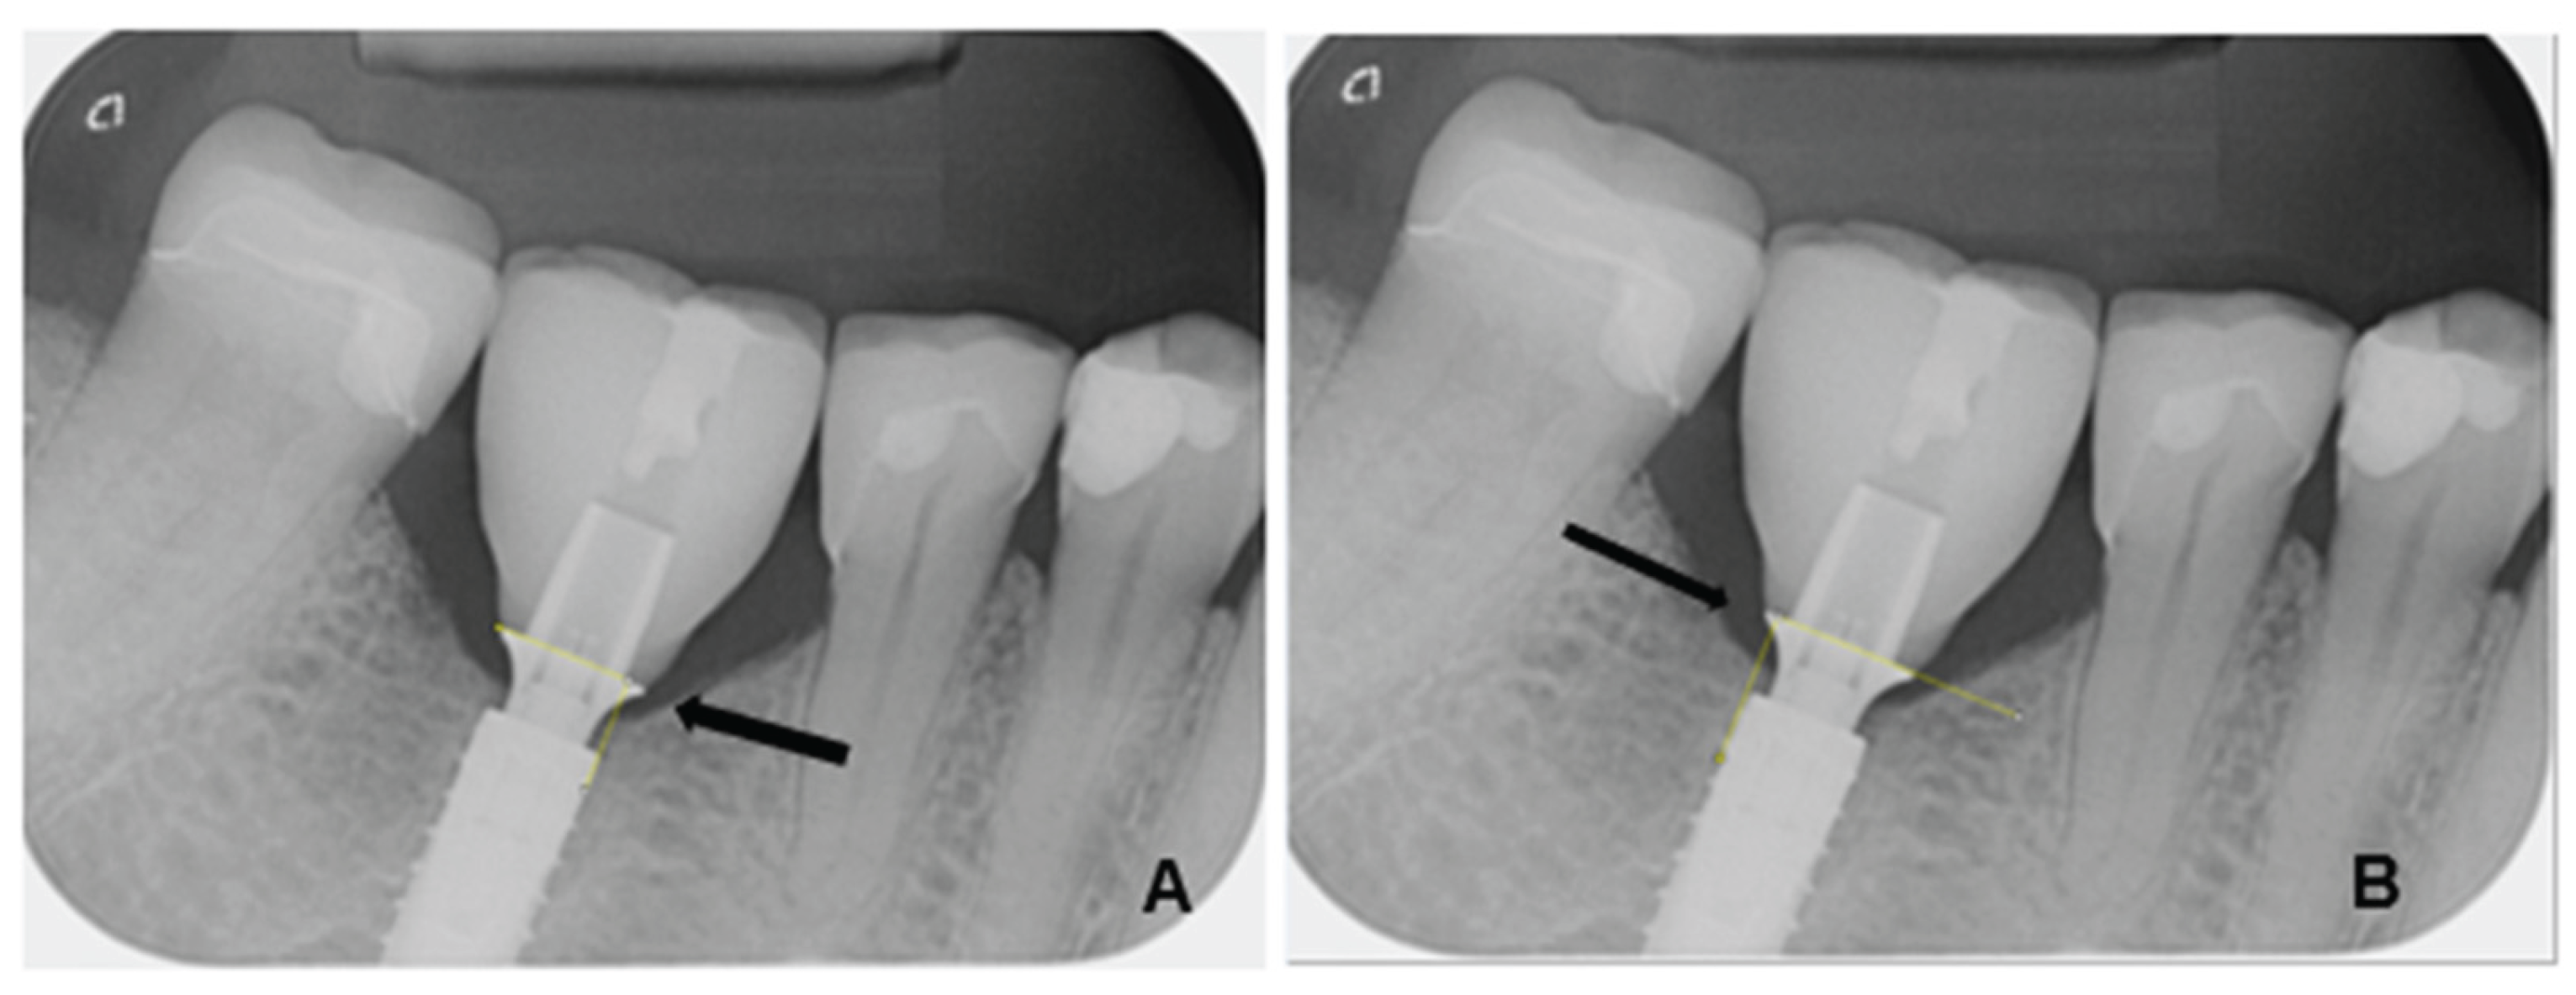

The radiological images were evaluated using the image analysis software ImageJ (Image Processing and Analysis in Java, version 1.53, macOS Monterey 12.7.4), a scientifically established open-source software for quantitative image processing. The measurements were calibrated based on the known diameter of each implant used. The measurement of marginal bone loss was performed both mesially and distally, orthogonally to the implant shoulder. The measurement was taken from the outer edge of the implant shoulder to the crestal bone edge (Figure 1). The examiners were calibrated prior to the measurement. In addition, several series of repeat measurements were performed at different times to reduce intraobserver variations.

All X-ray images were zoomed in for measurement to ensure maximum precision. Two bone measurements and one control measurement of the implant diameter were performed per patient at each measurement time point. The results were numbered consecutively, systematically documented, and archived in an Excel spreadsheet. Marginal bone loss was determined by calculating the difference between the baseline value (T0) and the follow-up measurements (T1).

Figure 1. Measurement of marginal bone height on an implant at the site of a premolar mesially (A) and distally (B). Bone height was measured mesially (A) and distally (B) between the titanium adhesive base and the alveolar ridge (yellow lines).